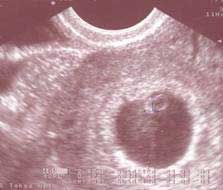

Už tady bylo mnohokrát napsáno a ještě víckrát potvrzeno, že chleba padá zásadně na namazanou stranu. Když jsem si myslela, že budu ještě pár měsíců kojit, nakoupila jsem si ochranné polštářky a za týden jsem musela s kojením přestat. První i druhé měsíčky po revizi dělohy přišli s neobvyklou intenzitou, sílou a délkou, tak jsem se zásobila hygienickými pomůckami a zdá se, že je nějakou dobu nebudu potřebovat. Na Nový rok měla moje doktorka službu, tak mě mohla v klidu vzít na ultrazvuk a prťátko je tam. Asi máme v domácnosti nějakého bacila :-).

Dva měsíce jsme nademnou obě kroutili hlavami. Já jsem byla přesvědčená, že těhotná být nemůžu, jen jsem nějaká porouchaná a nefunguju jak mám. Ona mi to potvrzovala negativními krevními testy, já to dokládala jednou čárkou na papírkových testech a obě jsme se přesvědčily na ultrazvuku, kde jsme nic neviděly. Nepomohla injekce Agolutinu, po které se do deseti dnů zaručeně jistý očekávaný důkaz měl dostavit. Po dvaceti dnech se nic nedělo a byl tady osudný Nový rok a oznámení, že jsem 6+3, počítáno podle velikosti, nikoliv podle měsíčků. Asi zabrala "výhrůžka", že začnu brát prášky, které se berou těsně před přechodem. Bilance - pohlaví neznámé, zdraví zjevné. Nejhezčí na tom je termín porodu, který zatím přesně souhlasí s narozeninama Aničky.